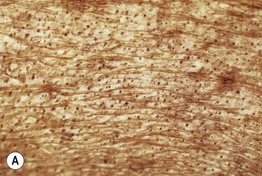

• Late: telangiectasias, follicular plugging (Fig. 36.10A), and occasional hemorrhagic bullae (Fig. 36.10B).

Fig. 36.10 Extragenital lichen sclerosus (LS). A Follicular plugging in a plaque of LS on the back of a patient with chronic GVHD. B Hemorrhagic bullae on the leg. A, Courtesy, Jean Bolognia, MD.